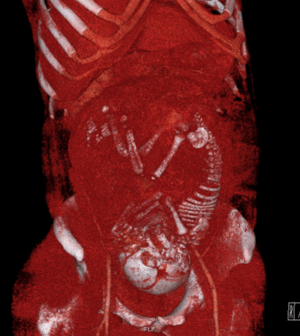

يستخدم التصوير بالرنين المغناطيسي عادة في النساء الحوامل المصابات بالألم البطني و / أو الألم الحوضي، أو في الاضطرابات العصبية المشتبه فيها، وأمراض المشيمة، والأورام، والعدوى، و / أو الأمراض القلبية الوعائية.[3] تعطي معايير الاستخدام المناسبة من قبل الكلية الأمريكية للأشعة تصنيف ≥7